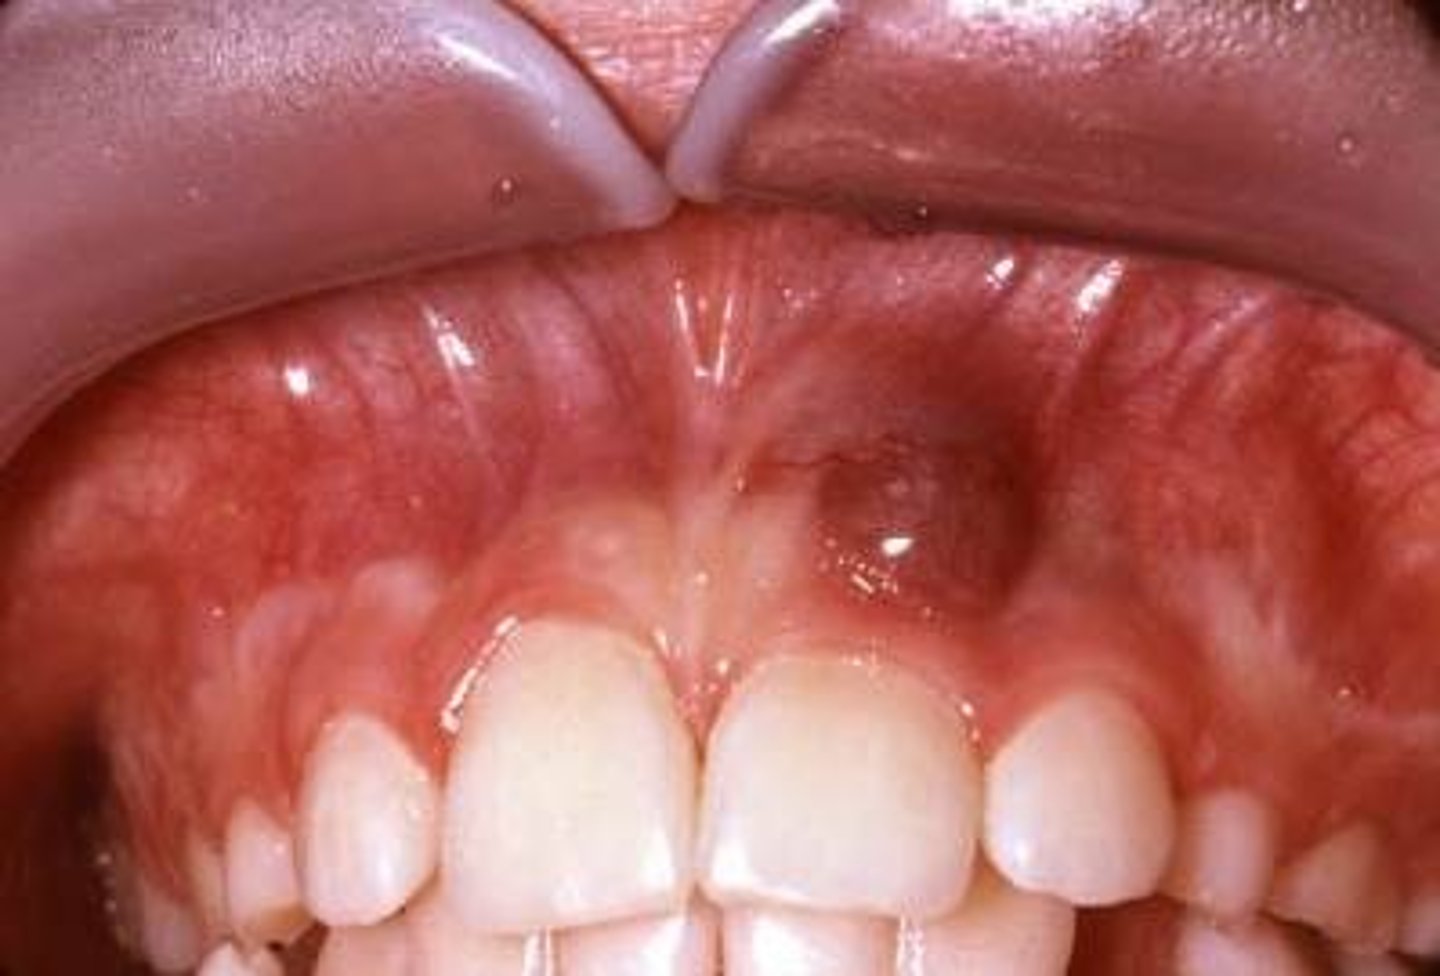

Ranula

A type of mucocele found on the floor of mouth. Ranulas present as a swelling of connective tissue consisting of collected mucin from a ruptured salivary gland duct, which is usually caused by local trauma. Only appears UNILATERALLY! Not bilateral.